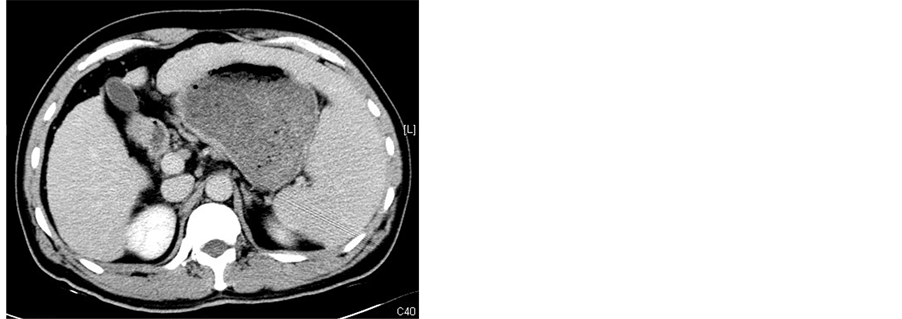

After splenic MWA, a 5.0 French catheter (Terumo, Tokyo, Japan) was inserted into the femoral artery with the Seldinger method after local anesthethia, celiac angiography and selective hepatic arterial angiography were routinely performed to observe the tumor blood-supply, distribution of hepatic arteries and collateral circulation routes (Figure 1(a)), the tip of the catheter was placed at the feeding artery of the tumor, and embolization was performed using an emulsion mixture of lipoidal ultra-fluid (Guerbet, France), perarubicin (50 mg/m2) and DDP (80 mg/m2). The maximum dose for embolization was based on the size of the tumor, blood supply and hepatic function of the patient. When the tumor was filled well with emulsifier, the embolization was terminated (Fig- ure 1(b)).

Figure 1. TACE treatment for a 63-year-old male case of HCC with splenomegaly and thrombocytopenia. (a) Celiac arteriography before TACE showing the tumor blood-supply image, as indicated by the arrowhead; (b) TACE is terminated when the three tumors were filled with emulsifier, as indicated by the arrowhead.